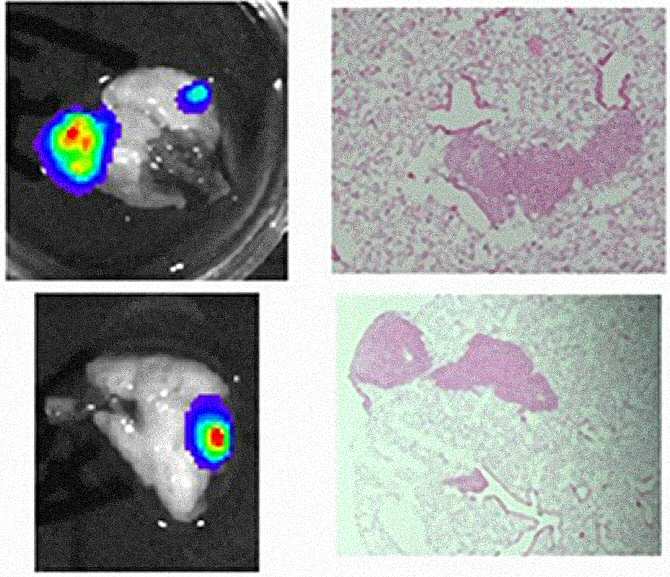

Metástasis pulmonares de ratones con líneas celulares de sarcoma de Ewing, vistas con bioluminiscencia (macrometástasis) a la izquierda o por tinción con H&E (micrometástasis) a la derecha. (Imágenes: BALB/c y Athymic)

Además, BIX01294 ralentizó el crecimiento del tumor primario y redujo el desarrollo de metástasis en más de un 40% en dos modelos de ratón con capacidad de generación de metástasis espontáneas, independientemente de la agresividad del tumor.